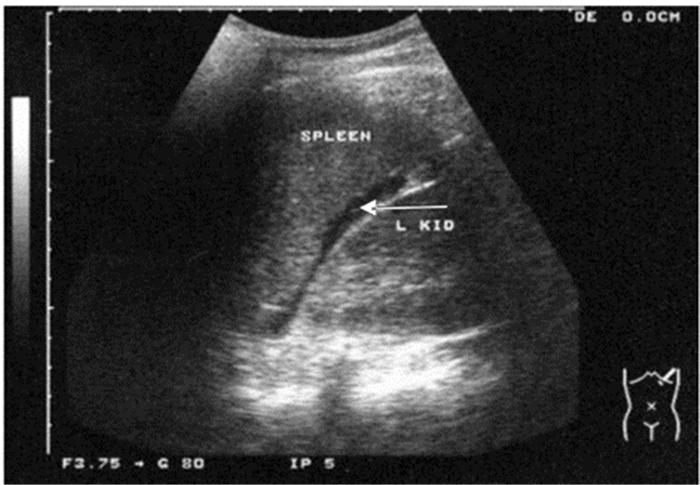

3.1.3 创伤的超声诊断的步骤及流程(1)创伤的超声诊断步骤:创伤患者床旁超声检查至少5个部位:①右上腹,也叫肝周切面、莫里森窝切面或右上1/4切面。如出现无回声区提示腹腔内出血(图 22-23)。②左上腹脾肾间隙,如出现无回声区亦提示腹腔内出血(图 24-25);③耻骨上/盆腔切面,如显示膀胱后或子宫后无回声区,提示盆腔出血可能(图 26-27);④剑突下切面,常用于探查心包有无无回声区(图 28),具体心包积液征象见2.1.2 常见异常超声心动声像图。⑤肺部超声,主要用于探查有无血气胸、肋骨骨折,具体征象见2.2肺超声。

| 图 24 脾肾间隙部位及正常超声影像 |

| 图 25 脾肾间隙出现无回声区 |